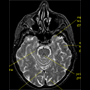

MRI of

horizontal section in

human